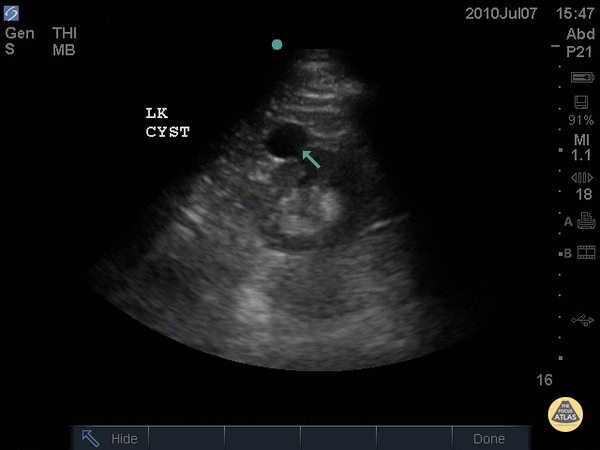

Renal/GU - Left Renal Cyst

This simple renal cyst can be identified as an anechoic structure with well-defined, thin walls. Sometimes septations can be seen. Large cysts might even demonstrate posterior acoustic shadowing. Dr. Justin Bowra et al.